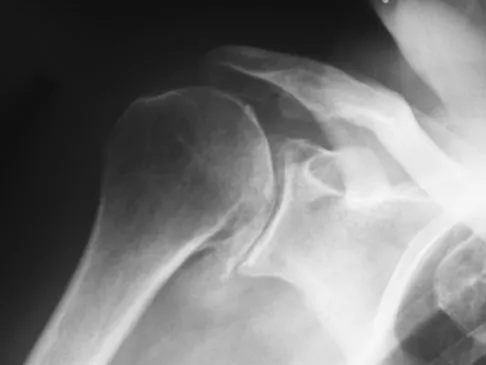

A 68-year-old man had a 3-year history of shoulder pain that failed to respond to nonsurgical management. Examination reveals forward elevation to 120 degrees and external rotation to 30 degrees. True AP and axillary radiographs and an axial CT scan are shown in Figures 1a through 1c. What management option would lead to the best long-term results?

A 66-year-old woman who previously underwent hemiarthroplasty 2 years ago for a fracture continues to have severe pain and loss of motion despite undergoing physical therapy. A radiograph is shown in Figure 2. What is the most likely reason that this patient has failed to improve her motion?